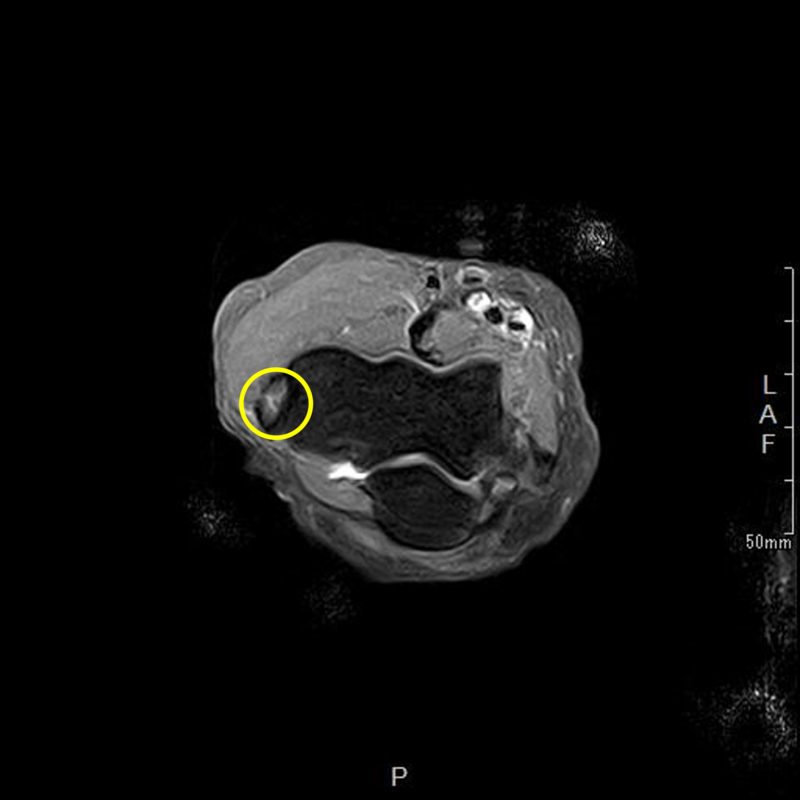

肘離断性骨軟骨炎(野球肘外側型)

肘の離断性骨軟骨炎(以下:OCD:osteochondritis dissecans)は上腕骨小頭という部位に好発することが多いです。

OCDを発見するにはレントゲンや超音波検査で上腕骨小頭軟骨下骨の状態を観察します。

軟骨下骨の不整像が軽微か不明の場合はMRI検査を行いOCDの確定診断を行います。

症例提示

12歳・男性・スポーツは野球(週2回/4年間)

2024年3月頃から外傷誘因なく疼痛出現。

2024年4月上旬、他院受診して超音波検査で軟骨が剝がれていると診断を受けたが経過観察のみ。

2024年5月、当院受診。レントゲン撮影をして離断性骨軟骨炎と診断されてリハビリ開始。

リハビリでは、徒手療法(マッサージ)・運動療法(筋力トレーニング ストレッチ)・物理療法を実施していましたが、

疼痛消失には至らず、組織修復を目的に体外衝撃波を実施しました。

体外衝撃波(拡散型圧力波治療)は、週1回の頻度で3回実施しました。